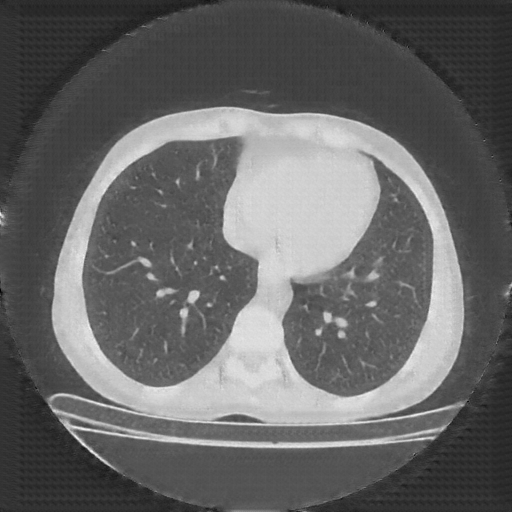

Generated VENOUS CT scan (A→B translation)

No window - Raw intensity values

Lung window (WL -600, WW 1500 β†’ Low βˆ’1350, High +150)

Mediastinum window (WL 40, WW 400 β†’ Low βˆ’160, High +240)